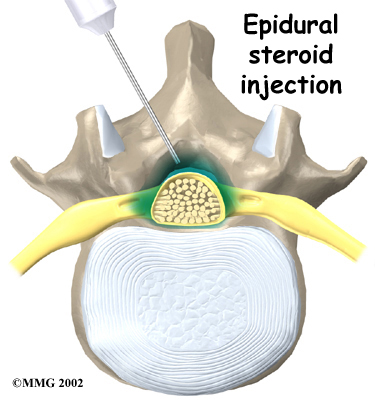

Some patients are given an (ESI). The spinal cord is covered by a material called dura. The space between the dura and the spinal column is called the epidural space. It is thought that injecting steroid medication into this space fights inflammation around the nerves, the discs, and the facet joints. This can reduce swelling and give the nerves more room inside the spinal canal.

Some patients are given an (ESI). The spinal cord is covered by a material called dura. The space between the dura and the spinal column is called the epidural space. It is thought that injecting steroid medication into this space fights inflammation around the nerves, the discs, and the facet joints. This can reduce swelling and give the nerves more room inside the spinal canal.

Research shows that a single steroid injection offers only short-term relief. Multiple injections can produce long-term, lasting pain relief. Epidural injections should be given using contrast-enhanced fluoroscopy. Fluoroscopy is an imaging technique used by the surgeon to guide the needle to the right spot during the procedure. This type of imaging improves the accuracy of medication delivery.